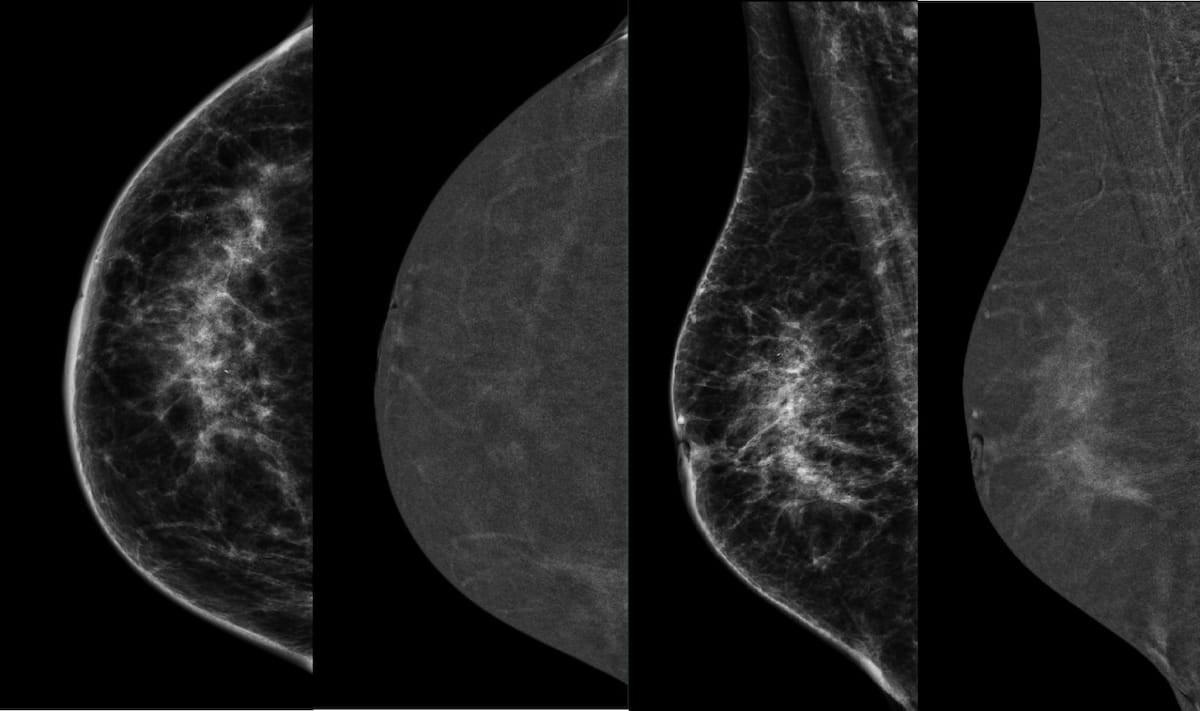

For women with dense breasts, abbreviated breast MRI and digital breast tomosynthesis (DBT) both offered greater than 98 percent sensitivity rates and greater than 94 percent negative predictive values (NPVs) for breast cancer detection, according to newly published research.